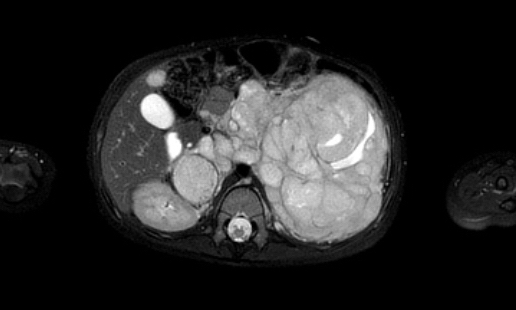

Example 2

Video về một bé gái ba tuổi có khối u lớn ở hông phải.

The remnant of the collecting system is dilated.

Same patient.

A tumor thrombus is present in the inferior caval vein.

Chuỗi ảnh MRI axial trọng số T2 cho thấy huyết khối u lan rộng đến mức tĩnh mạch gan. Lưu ý phần còn lại giãn rộng của hệ thống thu thập nước tiểu